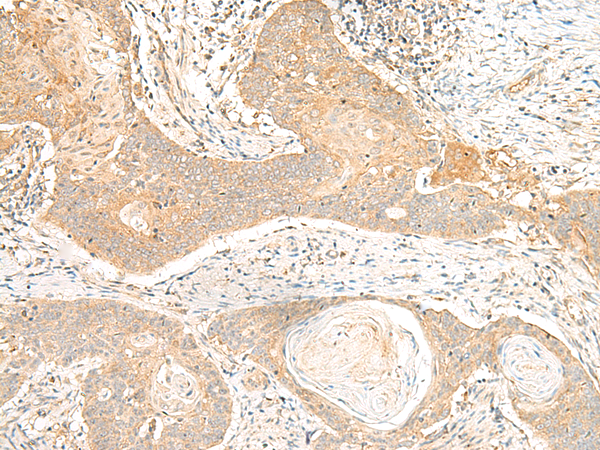

分类: 科研抗体货号: P13466别名: GLTSCR1应用: IHC反应种属: Human

-